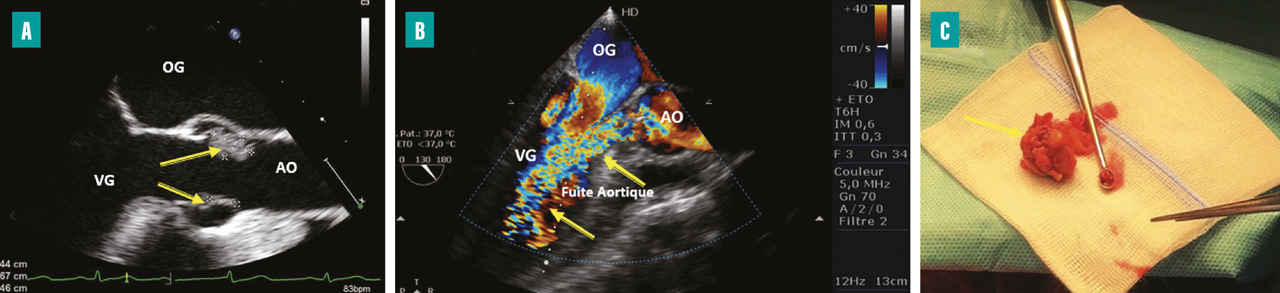

L’insuffisance cardiaque est la complication la plus fréquente (50 à 60 %) et la première cause de mortalité dans l’EI.3Un délabrement valvulaire important peut entraîner une fuite valvulaire sévère (

La surveillance de l’apparition ou de l’aggravation de signes d’insuffisance cardiaque au cours de l’évolution de l’EI est primordiale. L’auscultation cardiopulmonaire quotidienne fait partie des éléments clés de la surveillance. Les échographies transthoracique (ETT) et transœsophagienne (ETO) restent les examens de référence pour le diagnostic et la surveillance de l’évolution des lésions valvulaires.2

La recherche de signes de mauvaise tolérance échographique de la fuite (élévation de la pression télédiastolique du ventricule gauche, hypertension artérielle pulmonaire…) doit amener à discuter la chirurgie même si l’insuffisance cardiaque est cliniquement bien tolérée ou stable. Les indications opératoires pour insuffisance cardiaque sont discutées au sein de l’équipe pluridisciplinaire qui doit sélectionner les patients à opérer et planifier cette chirurgie en prenant également en compte les risques liés à l’intervention.4

L’apparition à l’échographie cardiaque d’un abcès périvalvulaire ou périprothétique aortique (fig. 3 ) ou mitral est une complication grave de l’EI. L’abcès est plus fréquent dans les EI sur prothèses valvulaires (50 à 80 % contre 10 à 40 % sur valves natives). L’ETO est plus sensible que l’ETT pour ce diagnostic (notamment pour les localisations postérieures)2 et le scanner cardiaque est très performant pour la recherche d’abcès sur prothèse. La détersion de l’abcès peut être à l’origine de fistules entre les différentes cavités cardiaques (fig. 4 ). La fistulisation se fait le plus souvent dans la chambre de chasse du ventricule gauche. Les fistules intracardiaques dans l’oreillette gauche ou droite peuvent être à l’origine d’un tableau d’insuffisance cardiaque et compliquent le geste chirurgical.